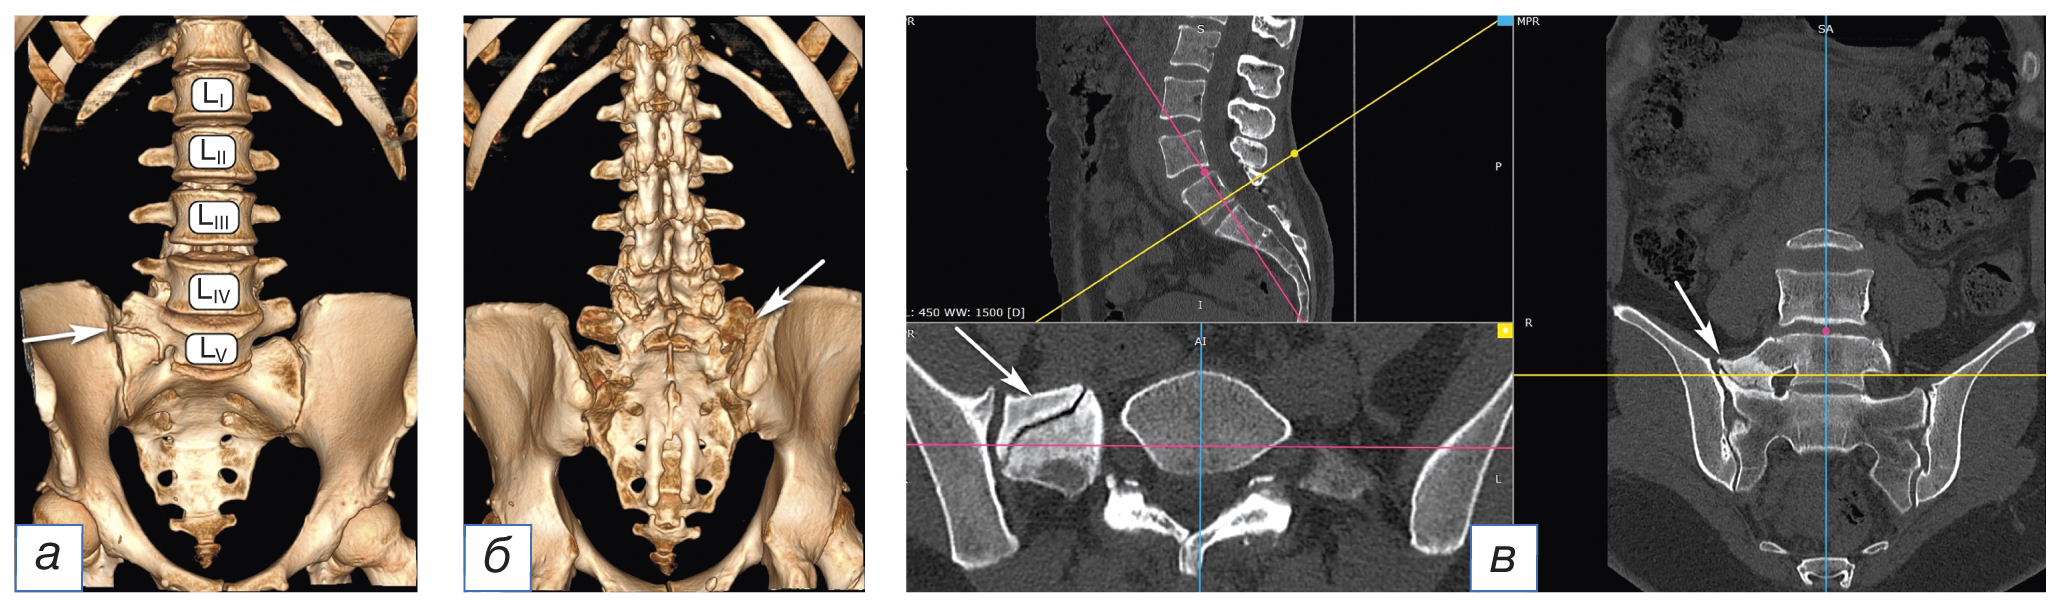

Заключение мультиспиральной компьютерной томографии (МСКТ): «Дегенеративные изменения поясничного отдела позвоночника. Узел Шморля тел LV и SI позвонков. Остеохондроз 2–3-го периода. Умеренное сужение межпозвонкового отверстия LV–SI. Сакрализация LV справа» (рис. 1).

Рис. 1. Сакрализация по результатам мультиспиральной компьютерной томографии: 3D-МСКТ, передняя проекция (а); 3D-МСКТ, задняя проекция (б); МСКТ-реконструкция с полипроекционным сканом (в). На уровне LV позвонка определяется аномалия пояснично-крестцового перехода по типу асимметричной правосторонней сакрализации позвонка LV с формированием неоартроза между массивным поперечным отростком и боковой массой крестца (белые стрелки). Тело позвонка LIV смещено вентрально на 0,45 см (антеспондилолистез I степени). Спондилоартроз LIV–LV III степени по D. Weishaupt [14]. Сакрализация LV позвонка, тип IIа по А.Е. Castellvi [15]

Fig. 1. Sacralization from a multispiral computer tomography scan: MSCT 3D front projection (а); MSCT 3D rear projection (б); MSCT reconstruction with a poly-projection scan (в). At the LV vertebra level, a lumbosacral junction anomaly is determined by the type of asymmetric right-sided sacralization of the LV vertebra with the formation of neoarthrosis between the massive transverse process and the lateral mass of the sacrum (white arrow). The body of the LIV vertebra is displaced ventrally by 0.45 cm (grade I antespondylolisthesis). Spondyloarthrosis LIV–LV III degree according to D. Weishaupt [14]. Sacralization of LV vertebra type IIa according to A.E. Castellvi [15]